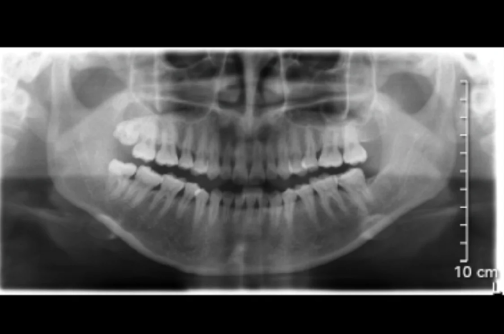

轻微牙周炎真后悔做了龈下刮治 牙周刮治后越来越严重了怎么办 编辑

轻微牙周炎到底要不要做龈下刮治主要是听取医生建议以及自己的选择,如果龈下刮治后恢复了那没有什么后悔的,但如果龈下刮治后更严重了,那代表是炎症没有控制好,需要每天牙齿清洁,好好维护,不然很难取到治疗效果的。

对于一些牙周炎比较严重的患者,龈下刮治可能是必要的治疗措施之一。牙周炎是一种常见的口腔疾病,它是由牙齿周围的牙龈组织受到炎症损害引起的。如果不及时治疗,牙周炎可能会导致牙齿松动、牙齿脱落等问题。

龈下刮治是通过专业的器械对于龈下的牙周组织进行深度清洁,包括根面清洗和病理性软组织的处理。这可以去除龈下的菌斑和牙石,减少牙齿周围的炎症,促进口腔组织愈合,从而达到预防和治疗牙周炎的目的。